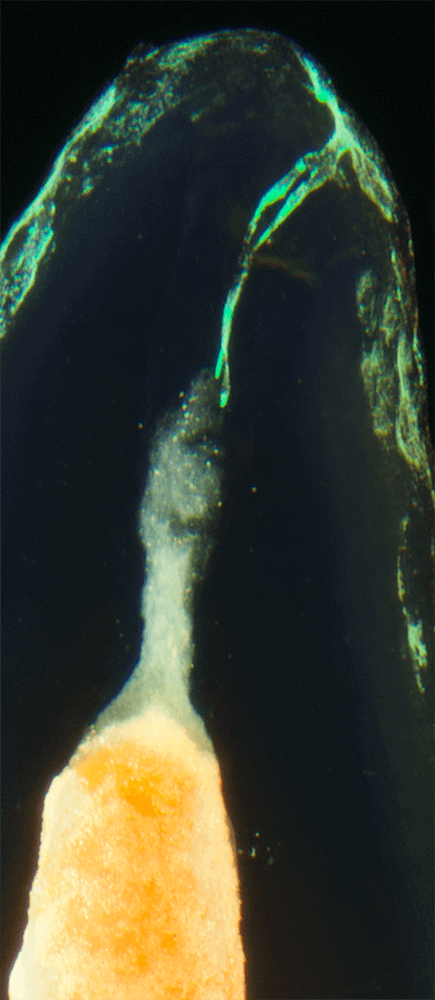

Das Verfahren, Zähne in durchsichtige Präparate zu überführen ist schon über 100 Jahre alt. Aber erst durch die Weiterentwicklung der alten Technik und die Kombination mit moderner Fotografie sowie der Entwicklung eines geeigneten Gefäßes zur Fotografie ist es meinem Vater Dr. Holm Reuver gelungen, einzigartige Bilder vom Inneren der Zähne aufzunehmen.

Die Bilder sind in verschiedenen Größen wählbar und auch als POPART-Variante erhältlich. Sie sind hervorragend geeignet für die Beratung von Patienten vor endodontischen Behandlungen, aber auch ein beliebter Eyecatcher im Wartezimmer. Außerdem haben die Bilder einen bedeutenden Stellenwert für die Erforschung der Pulpatopografie und für die Lehre im Bereich der Endodontie.

und die von ihm angefertigten Bilder, laden wir Sie ein, seine Begeisterung zwischen Wissenschaft und Kunst mit ihm zu teilen.